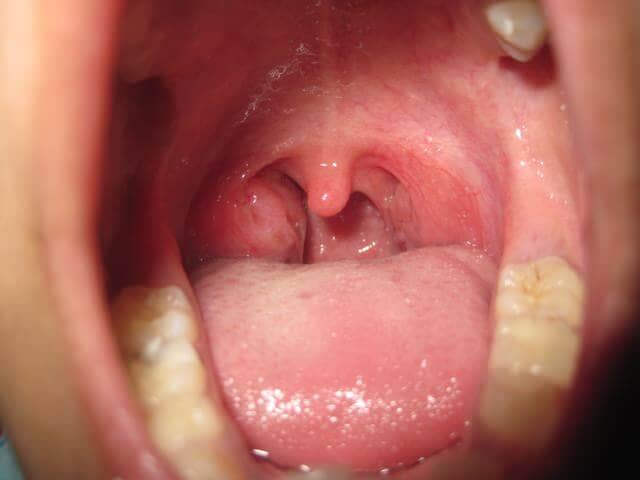

Δείτε ακόμη Πύον στις αμυγδαλές: τι ασθένειες μπορεί να έχετε (εικόνες)

Σύμφωνα με το βρετανικό σύστημα υγείας, NHS, η ασθένεια είναι πολύ μεταδοτική και μπορεί να εξαπλωθεί με μεγάλη ταχύτητα. Πρόκειται για βακτήριο που εντοπίζεται στη μύτη, σύμφωνα με το protothema, στο λαιμό ενώ μπορεί να προκαλέσει μόλυνση στο δέρμα όπως και πονόλαιμο. Από τη στιγμή που κάποιος εκτεθεί στο βακτήριο χρειάζονται από δύο μέχρι πέντε μέρες για να εμφανίσει πυρετό.

Η ασθένεια ξεκινά με κοινά συμπτώματα γρίπης, δηλαδή υψηλό πυρετό, πονοκέφαλο, πονόλαιμο και πρησμένους αδένες. Στην αρχή της νόσου, τα βακτήρια μπορεί να προκαλέσουν την εμφάνιση λευκών σημαδιών στη γλώσσα, η οποία τελικά ξεφλουδίζει, καταλήγει πρησμένη και καλυμμένη από εξογκώματα.